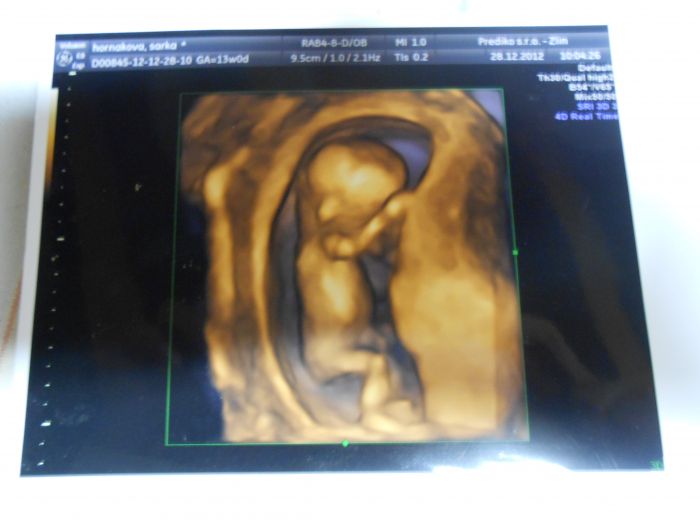

Jinak já jsem ze 3D měla krásnou fotečku ze 13.týdne.

3D uzv se mi libyl, delali mi ho ve 13 tydnu, akorat kluci mi rekli,ze ze to spis vypada na Martana a ne na jejich sourozence

; Tady v Belgii se za snimky nic neplati a pri bezne prohlidce ho davaji take normalne, nekdy jich mam i vice.